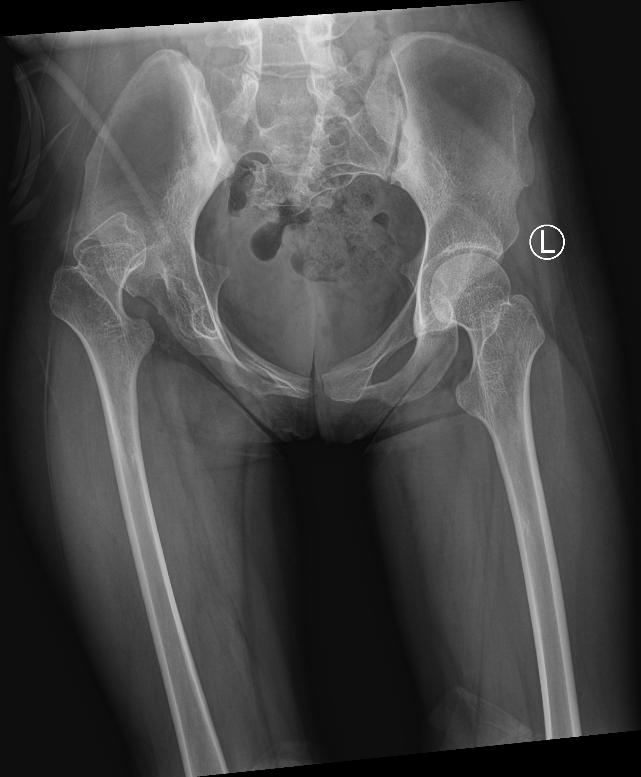

据了解,小肖今年18岁,曾因脊髓瘤多次在外院接受手术,并患有双侧马蹄足、小便失禁等后遗症,需长期携带尿管生活,因右髋关节发育不良在我院治疗。据患者反映,右侧髋关节疼痛难忍,吃止疼药已无法减缓疼痛。考虑到患者病情比较复杂,陈柯主任和他的团队根据患者病史、影像资料、体格检查等信息制定了详细的诊疗方案,于2024年7月15日给患者做了右侧全髋关节置换术,现术后恢复良好,右髋关节疼痛明显缓解,关节功能基本恢复。